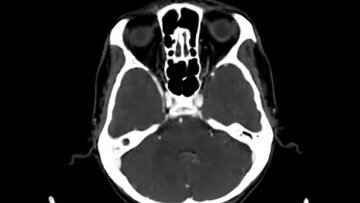

Что покажет КТ головного мозга и шеи (видео)